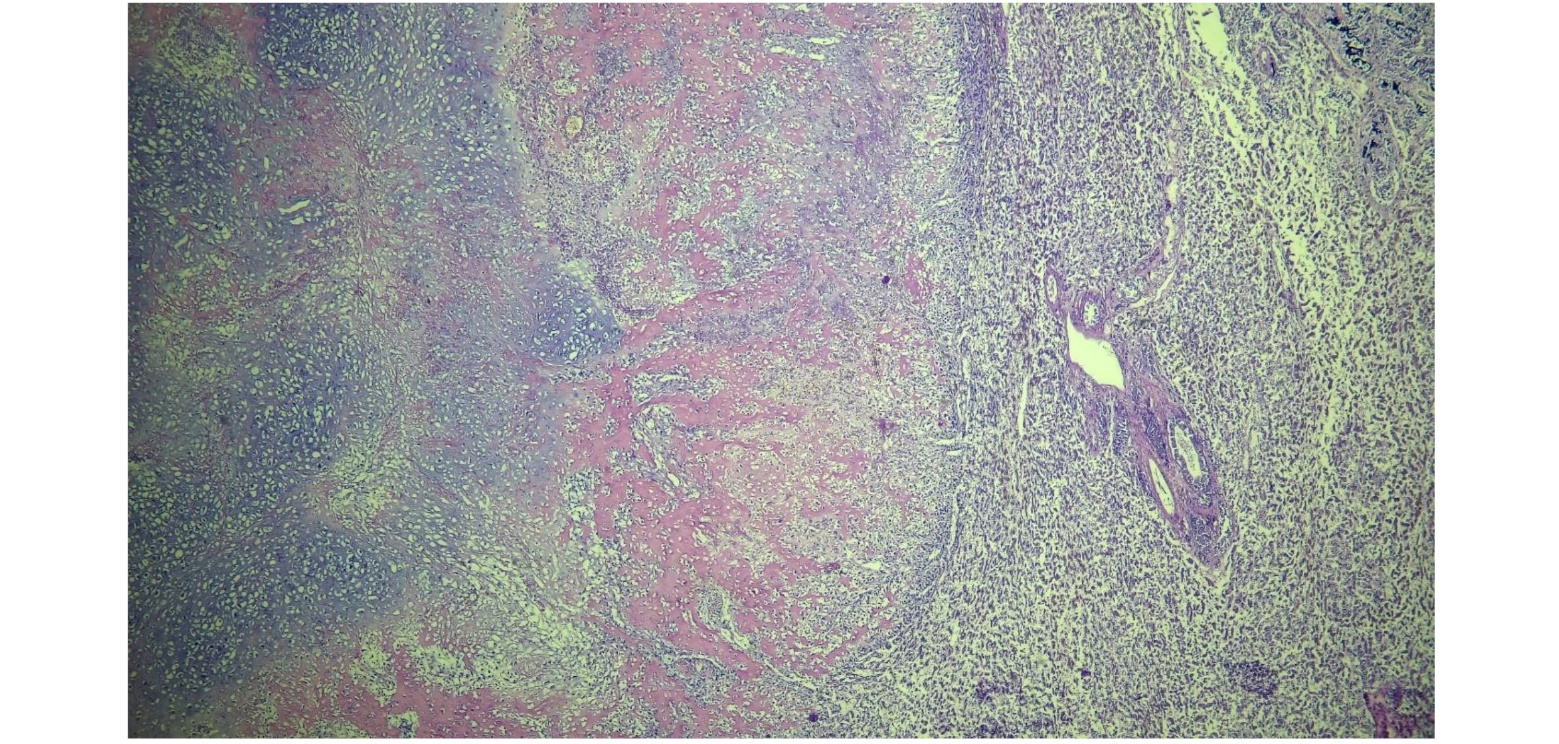

Besides not possible to visualize in macroscopy, the lungs also presented the same microscopic examination of all the regions (Fig.2): a marked cellular infiltrate been irregular, multifocal and non-encapsulated. The cells exhibited an irregular tubule-papillary arrangement, sometimes isolated amidst intense fibrocollagenous stroma. They were polyhedral to elongated, intermediate in size, with moderate to scarce, eosinophilic, vacuolated to homogeneous cytoplasm. They had a rounded, centralized nucleus with coarsely dotted chromatin and 0 to 3 intermediate and conspicuous nucleoli. Marked anisokaryosis, anisocytosis and moderate cellular pleomorphism were observed. The neoplasm exhibited low mitotic activity, with 7 mitotic figures observed in 2.37mm², with moderate binucleated and multinucleated cells (Fig.3). Additionally, presence of an intense multifocal to coalescent necrosis and intense, multifocal bone and cartilaginous metaplasias (Fig. 4).

Figure. 4. Presence of an intense, multifocal, bone and cartilaginous metaplasias.

Mesotelioma are subclassified as epithelioid, sarcomatous, or mixed/biphasic types in veterinary (Meuten, 2020). In humans, they are subdivided into 17 different histologic subtypes, of which papillary, tubular, solid, sclerosing, cystic, and deciduoid subtypes have been reported in the peritoneum of domestic animals (Meuten, 2020). The papillary subtype appears as branching outgrowths of large and polygonal cells that are supported by a central stromal core. and may contain glycogen‐containing vacuoles. The tubular type form tubular structures over the serosal surface. When the neoplastic cells are arranged in solid masses, nests, or trabeculae, it is classified as a solid. A sclerosing/desmoplastic mesothelioma contains few neoplastic mesothelial cells accompanied by large quantities of non‐neoplastic fibrous tissue that may include cartilage or bone. Distant metastases are reported such as lymph nodes, adrenal glands, lung and brain (Meuten, 2020).